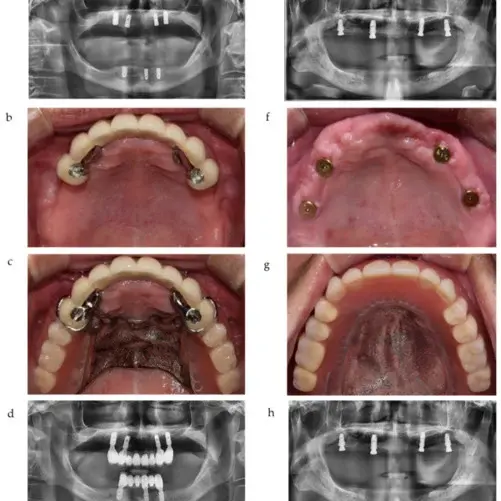

Before and After

SEE OUR RESULTS

Implant-supported removable partial dentures (ISRPDs) represent a convergence of traditional removable prosthetics and contemporary implantology, orchestrating a symbiotic relationship that leverages the stability of implants while retaining the adaptability of a removable prosthesis. The structure essentially incorporates dental implants, usually integrated into the jawbone, which engage with specific attachments housed within the partial denture. This union not only confers enhanced stability and retention to the denture but also mitigates the classic limitations of conventional removable partial dentures, such as movement during function and potential tissue irritation. The functionality extends to improved masticatory efficiency, enriched aesthetic harmony, and enhanced prosthetic longevity, while still permitting the patient to remove the prosthesis for hygiene and maintenance.

The procedural journey towards ISRPDs encompasses a blend of surgical and prosthetic phases that harmoniously integrate the placement and restoration of dental implants with the fabrication of a removable partial denture. Initial phases involve comprehensive evaluations, radiographic analyses, and treatment planning, which are followed by the surgical placement of dental implants in the jawbone. Following an appropriate healing and osseointegration period, precision attachments are affixed to the implants, and the corresponding removable partial denture is fabricated with complementary receptacles, ensuring a secure yet removable engagement. Contrasting with conventional dentures, the journey involves surgical components and a more intricate prosthetic orchestration to harmonize the implant and removable elements, culminating in a solution that combines the merits of stability and removability.